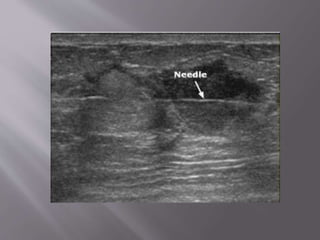

See the needle entering the peritoneal cavity obliquely from just

beneath the indicator marker.

See the needleentering the peritoneal cavity obliquely from just beneath the indicator marker.